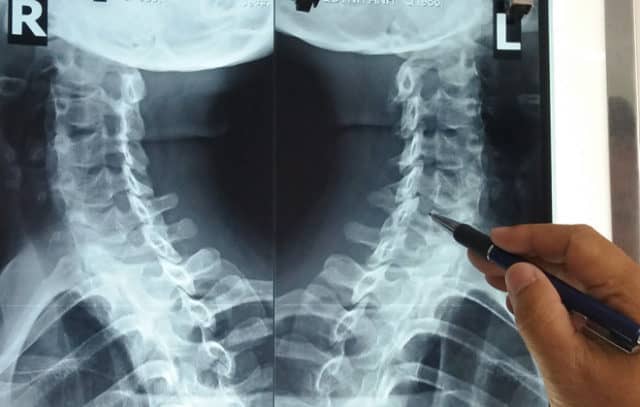

2. X-quang cột sống cổ bình thường hoặc có các triệu chứng của thoái hóa hoặc xuất hiện gai xương

3. Cộng hưởng từ hoặc CT-scan: Vị trí, mức độ rễ thần kinh bị chèn ép, nguyên nhân chèn ép (thoát vị đĩa đệm, gai xương)